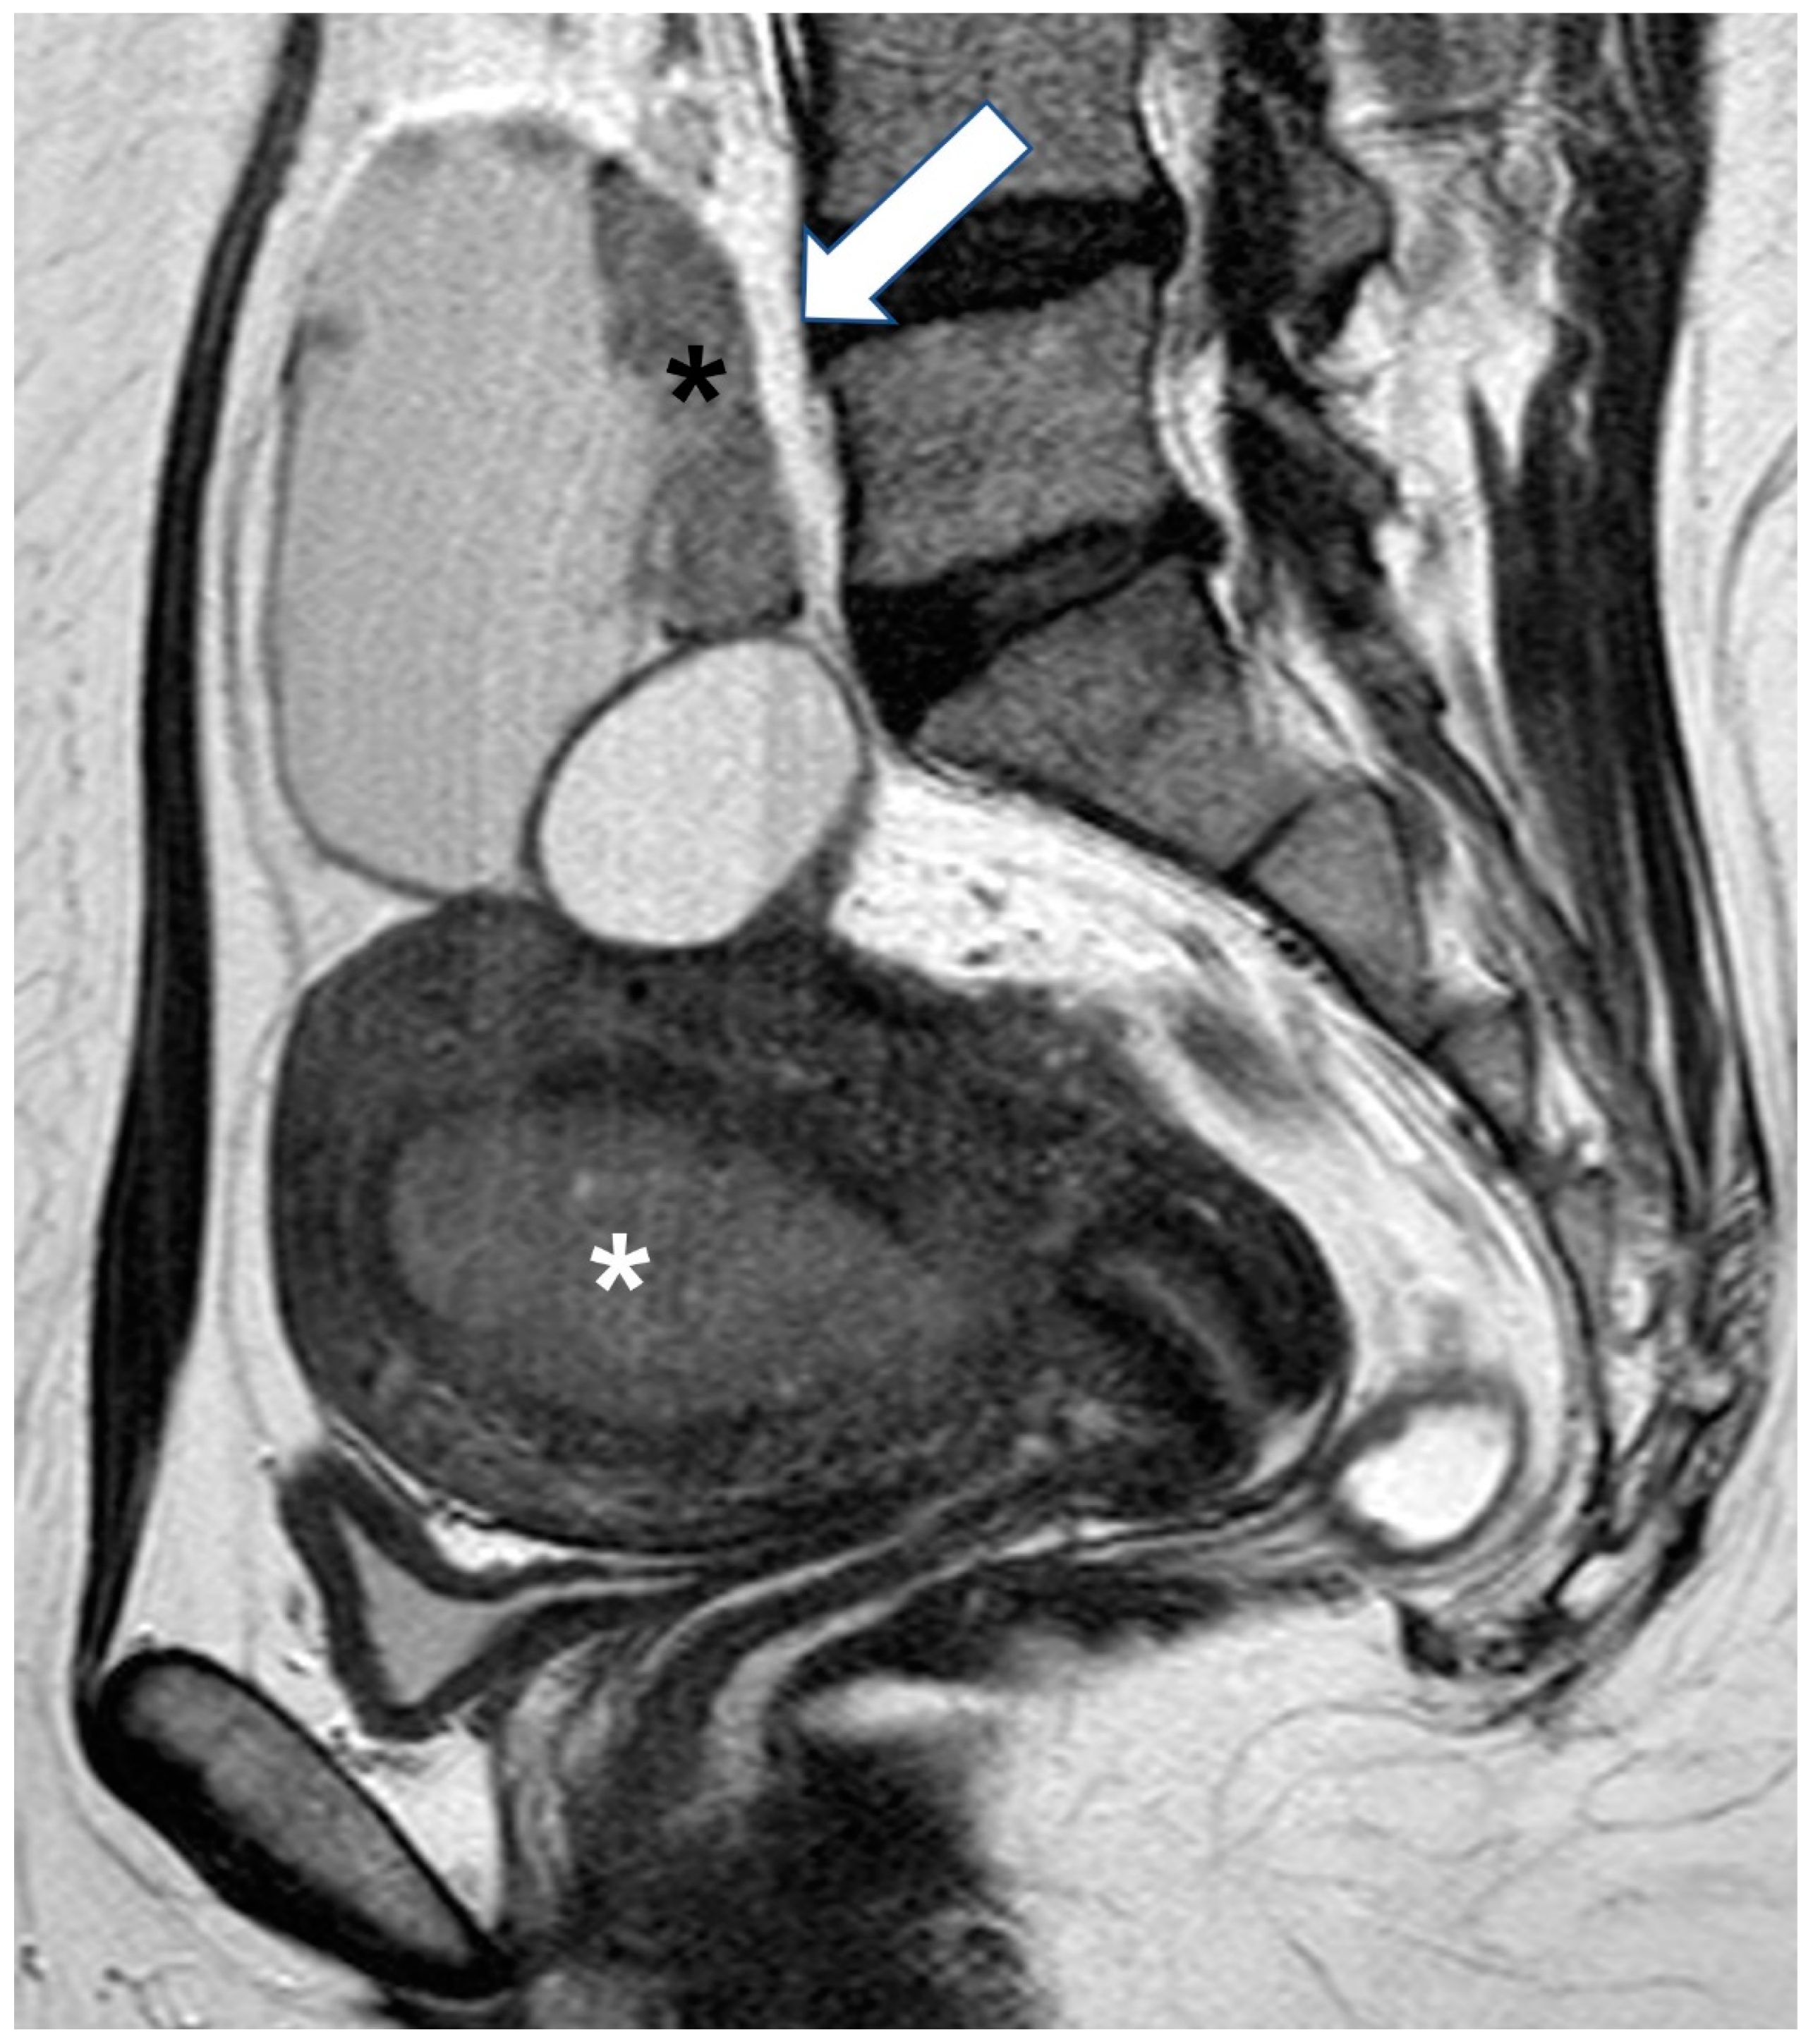

2.5. Pregnancy

2.5.3. Epithelial Ovarian Cancer